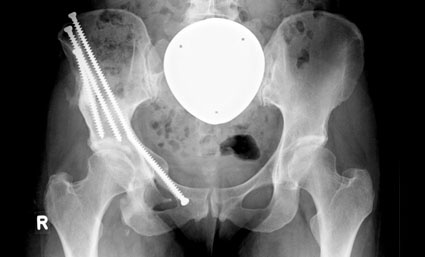

Heutzutage ist in der Regel davon auszugehen, dass Kunstgelenke eine durchschnittliche Haltbarkeit von ca. 15 Jahren bei regelrechter Implantation und adäquatem Verhalten des Patienten ermöglichen. Findet sich bei einem jüngeren Patienten eine Gelenkfehlstellung, wie z.B. eine Hüftdysplasie, dann ist hier bei noch guter Knorpelsituation immer eine Rekonstruktions-Maßnahme, d. h. eine operative Korrektur der Gelenkfehlstellung angezeigt. Es handelt sich hierbei um aufwendige, komplexe rekonstruktive Operationen, die entsprechenden Hüftzentren vorbehalten sein sollten.

Neben der häufigsten knöchernen Hüftdeformität der Hüftdysplasie stellt das sogenannte femoro-acetabuläre Impingement die häufigste zur Hüftarthrose führende Deformität dar. Bei mangelhaften Überdachungen des Hüftkopfes (Hüftdysplasie) wird die fehlstehende Hüftpfanne durch eine dreifache Knochendurchtrennung im Beckenbereich mobilisiert und ihre Position anschließend korrigiert, um eine normale Hüftüberdachung als Ziel der Operation zu erlangen.

Ist jedoch der Hüftgelenksverschleiß derart fortgeschritten, dass Gelenk erhaltende korrigierende Operationsmaßnahmen nicht mehr infrage kommen, und zeigt der Patient einen nicht mehr tolerablen Leidensdruck, der mit konservativen, nicht operativen Therapiemaßnahmen nicht mehr zu beherrschen ist, dann steht die Kunstgelenkversorgung (Hüft-Totalendoprothese) am Ende der therapeutischen Möglichkeiten.

Die Hüft-Totalendoprothese ist eine segensreiche, sehr erfolgreiche operative Maßnahme, die in aller Regel dem schmerzgeplagten Coxarthrose-Patienten wieder eine schmerzfreie Beweglichkeit und Mobilisierung ermöglicht. Sicherlich stellt die Hüft-Totalendoprothese die letzte Möglichkeit im Rahmen der verschiedenen auch operativen Therapieformen dar und bleibt für den Patienten mit vollständigem Hüftgelenksverschleiß die Therapiemaßnahme der Wahl.

Moderne, zementfrei implantierte Hüftprothesen-Komponenten zeigen in Langzeitstudien eine Haltbarkeit von 15 bis 20 Jahren, sofern es sich um bewährte Implantate handelt, die mit entsprechend hoher Erfahrung und Exaktheit operativ implantiert wurden.